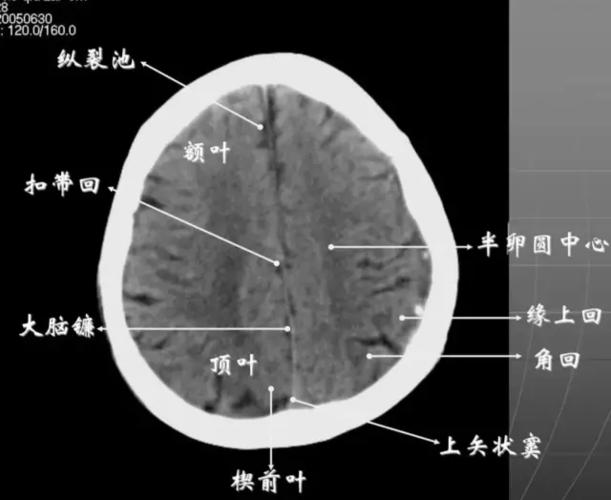

简明又详细的头部ct读片详解,收藏_脑室